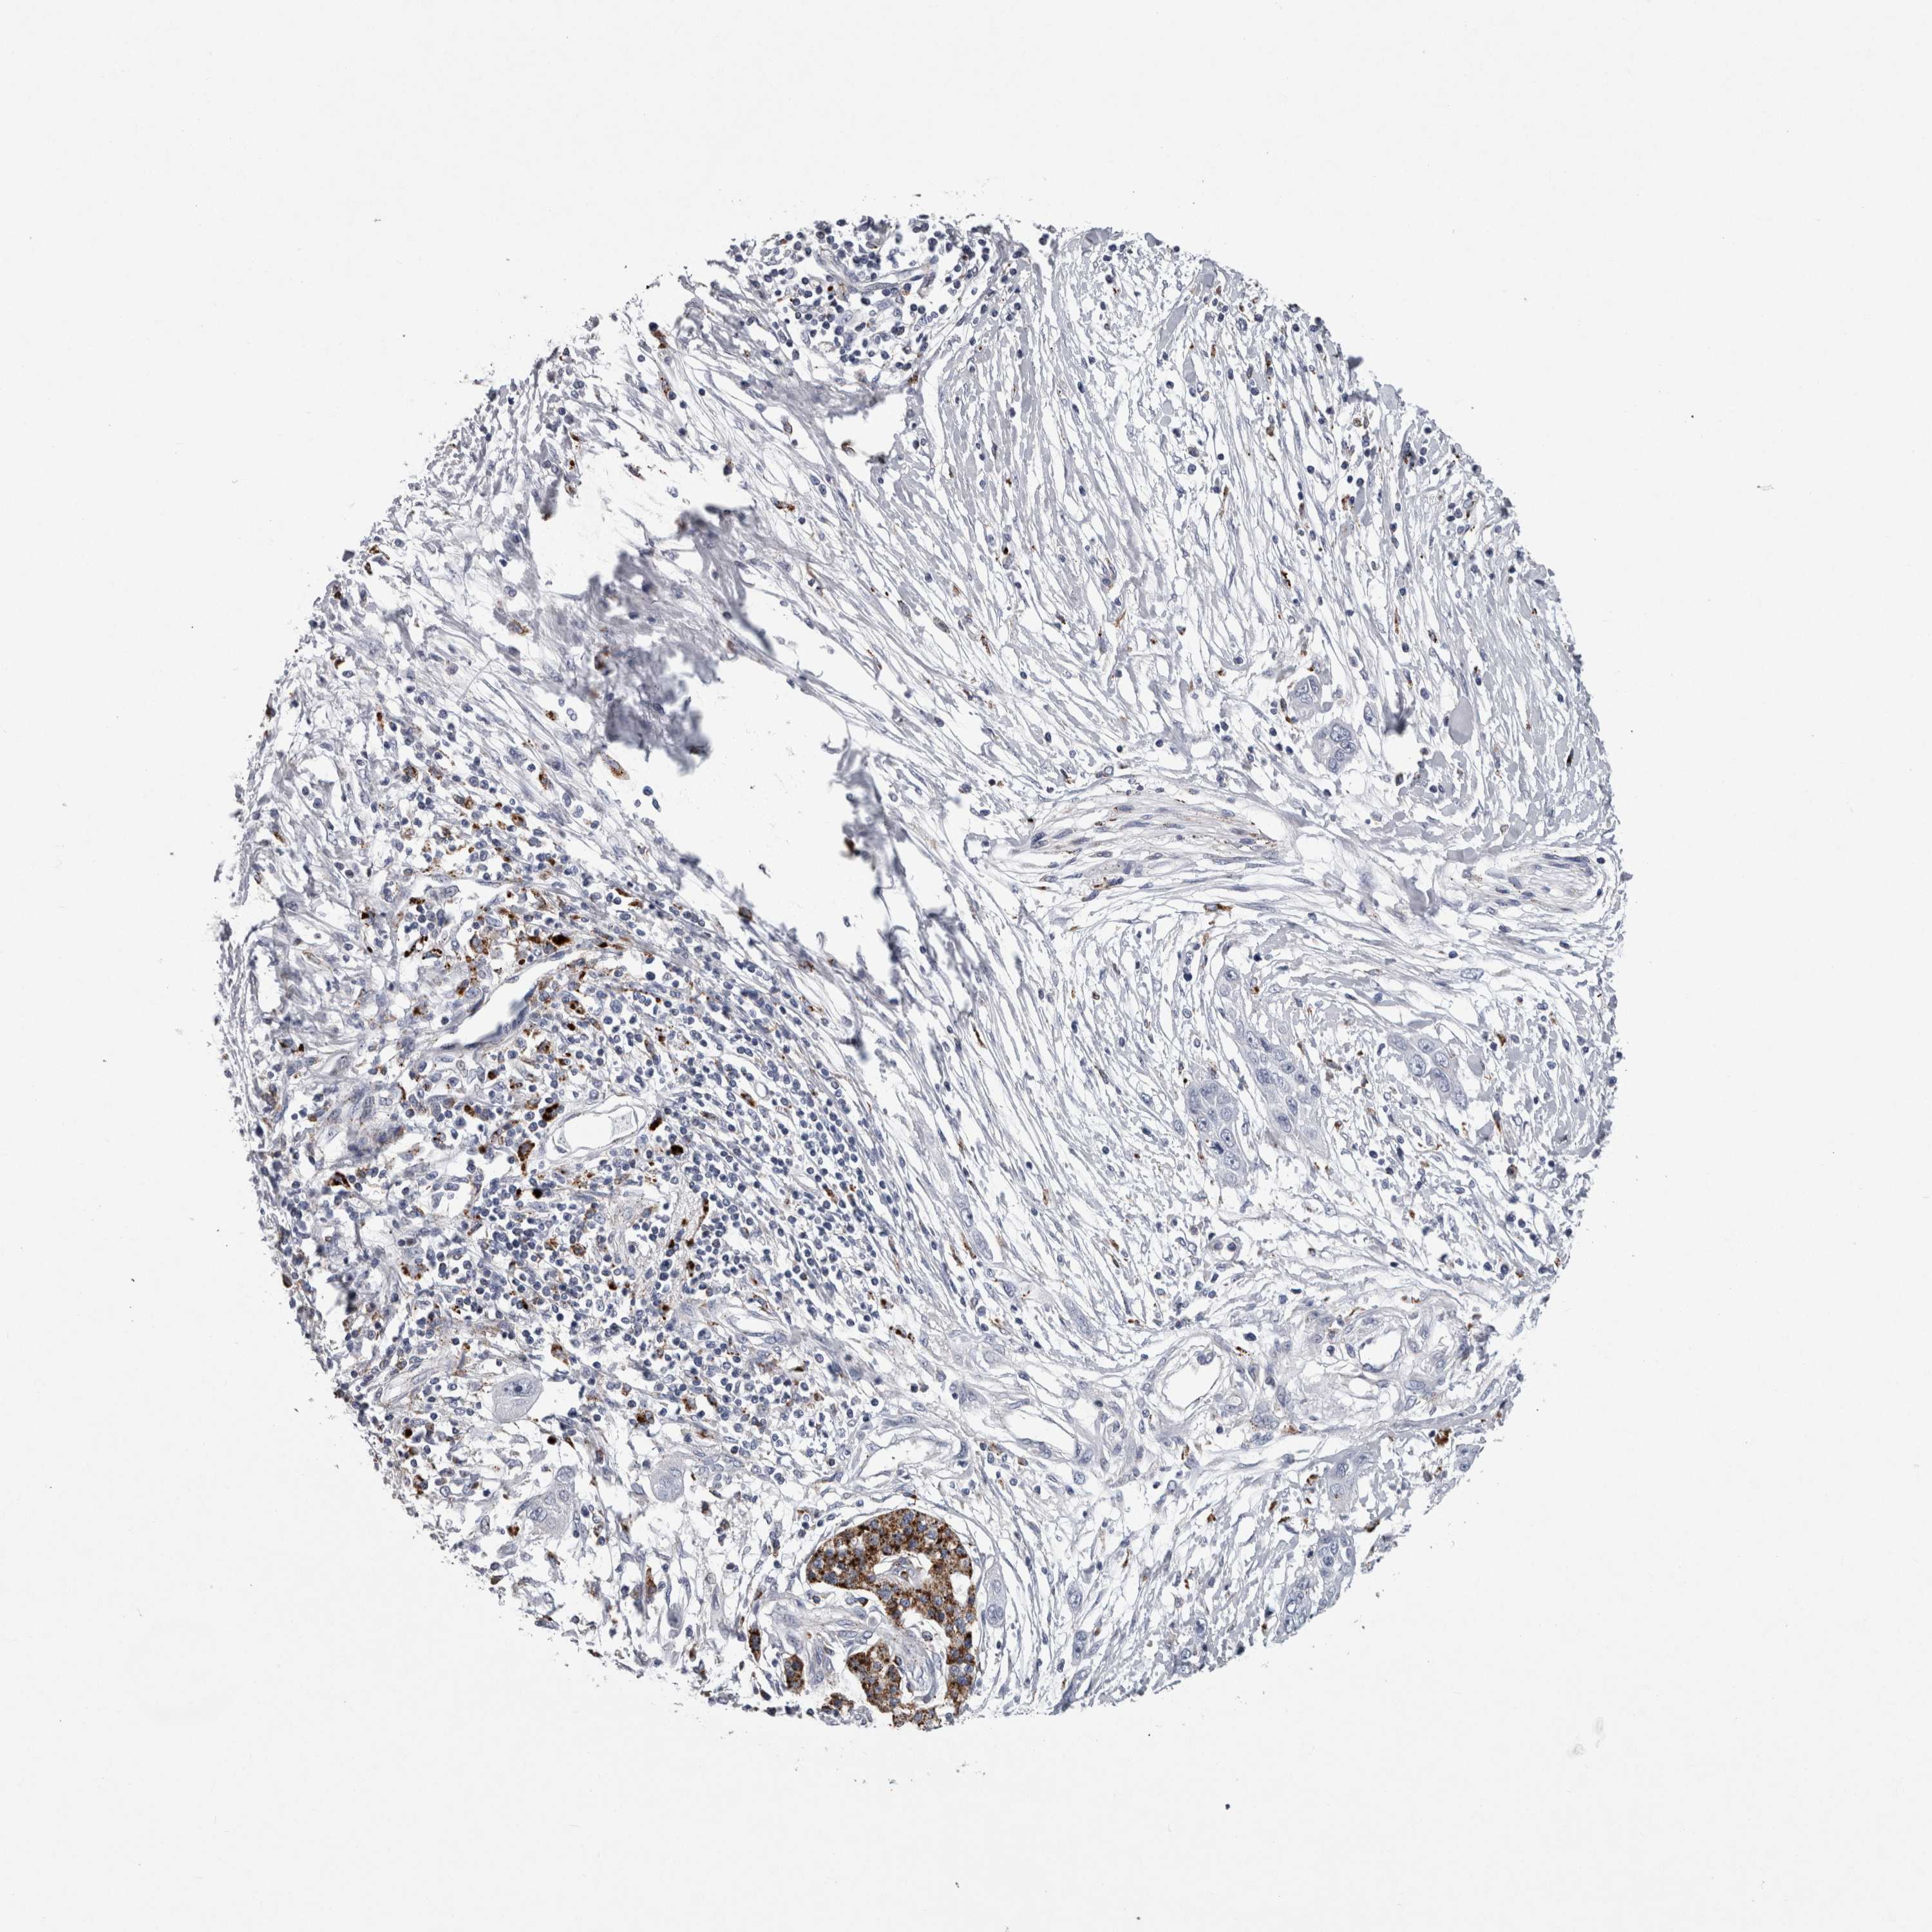

PANCREATIC CANCER - Protein expressioni

A mouse-over function shows sample information and annotation data. Click on an image to view it in a full screen mode. Samples can be filtered based on level of antibody staining by selecting one or several of the following categories: high, medium, low and not detected. The assay and annotation is described here.

Note that samples used for immunohistochemistry by the Human Protein Atlas do not correspond to samples in the TCGA dataset.

Antibody stainingi

Antibody staining in the annotated cell types in the current human tissue is reported as not detected, low, medium, or high, based on conventional immunohistochemistry profiling in selected tissues. This score is based on the combination of the staining intensity and fraction of stained cells.

Each image is clickable and will lead to virtual microscopy that enables deeper exploration of all samples and also displays staining intensity scores, fraction scores and subcellular localization as well as patient and tissue information for each sample.

Antibody HPA021282

Antibody CAB025541

Staining

High

Medium

Low

Not detected

Intensity

Strong

Moderate

Weak

Negative

Quantity

>75%

75%-25%

<25%

None

Location

Nuclear

Cytoplasmic/membranous

Cytoplasmic/membranous,nuclear

Adenocarcinoma, NOS